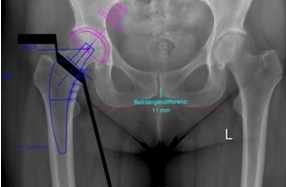

Sollte bei Ihnen eine Endoprothese in Frage kommen, wird durch Beurteilung verschiedener Faktoren der Prothesentyp aus dem o. g. Portfolio für Sie ausgesucht. Zudem wird beurteilt, welcher Zugangsweg, ob minimalinvasiv oder seitlicher Standardzugang, für Sie in Frage kommt. Hierbei gehen wir gerne auf Ihre Vorstellungen ein und wägen sorgfältig unsere Überlegungen mit Ihnen ab.

- Freitag T, Reichel H: Primäre Hüftendoprothetik – OP-Technik: Präoperative Planung. In: Perka C, Heller K (Hrsg.) AE-Manual Endoprothetik der Hüfte, Springer, 2024, S. 327-336

- Freitag T, Reichel H: Primäre Hüftendoprothetik – OP-Technik: Präoperative Planung; AE- Manual der Endoprothetik 2022 DOI: 10.1007/978-3-662-55485-2_79-1